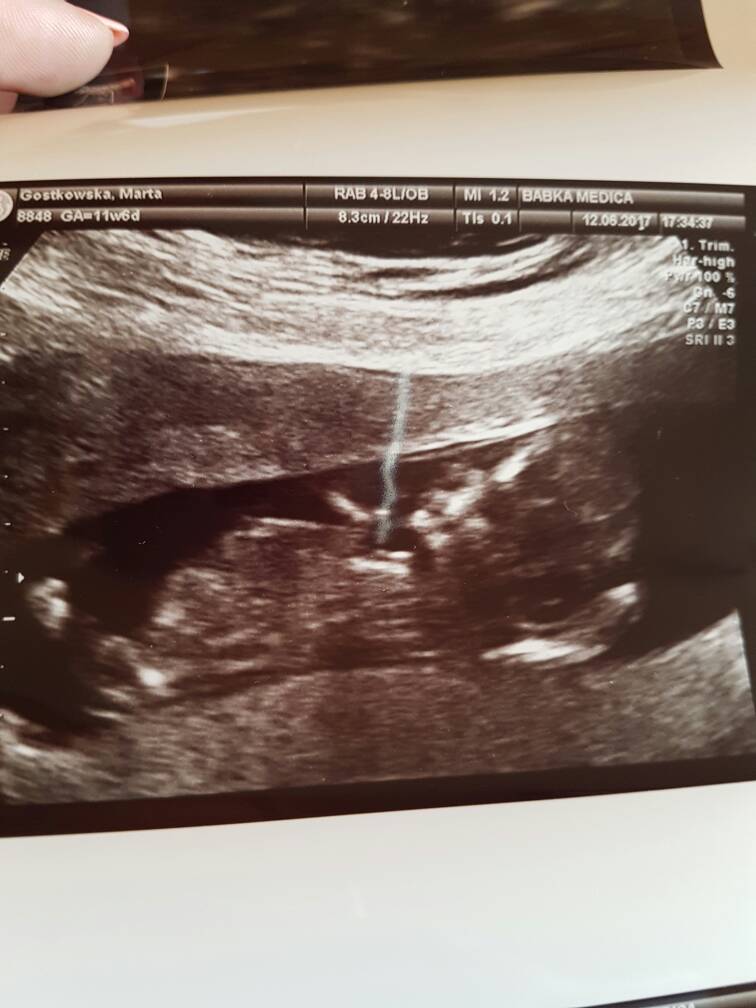

Wszystko dobrze. Dzidzius ma 12tyg6 dni według usg czyli prawie tydzień starszy niż z OM.

6,6 cm człowieka [emoji7]

Przezierność karkowa 1,51mm

Ryzyko wad bardzo niskie.

Niestety dzidzius zacisnąl nóżki i nie pokazał co tam ma.